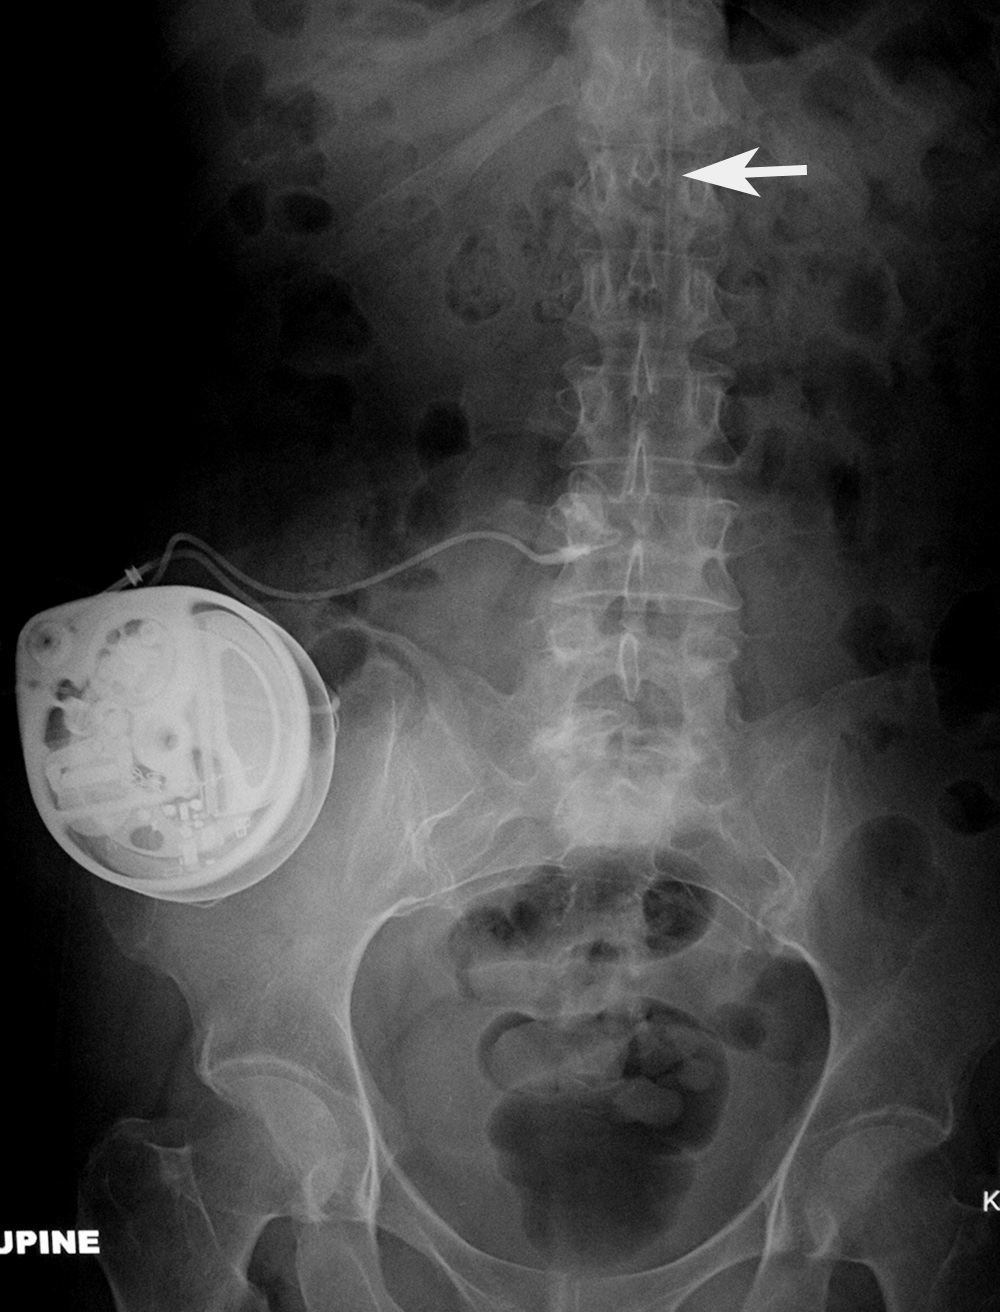

Baclofen intrathecal delivery pump AP view |

Baclofen intrathecal delivery pump lateral view |

The catheter (arrow) goes into the lower thoracic spinal subarachnoid space. |

The catheter (arrow) goes into the lower thoracic subarachnoid space. |

| The catheter is in the lower thoracic subarachnoid space. It exits in an anterior abdominal delivery pump. From Hunter, 2004 |